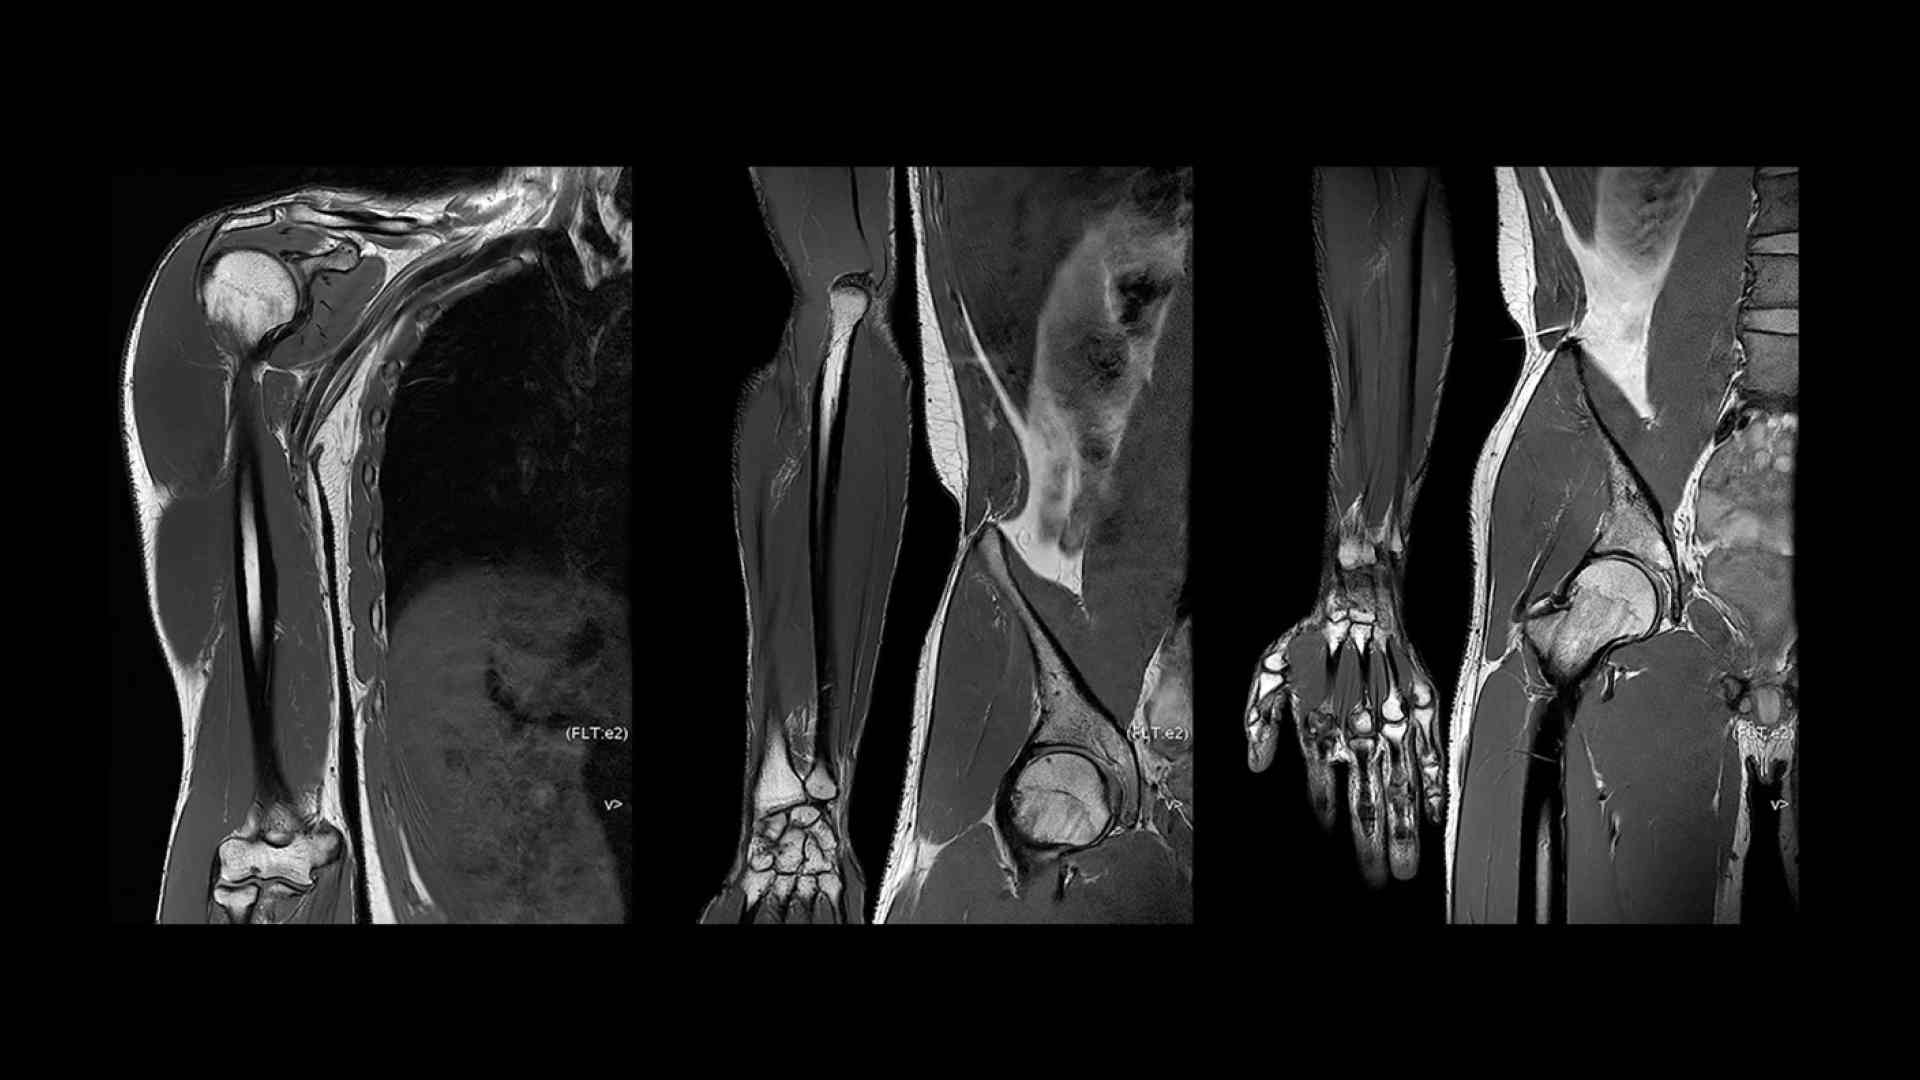

Revolutionary, deep-learning-based reconstruction techniques such as AIR™ Recon DL provide sharper, clearer, and accurate images

Pin-sharp image quality and exceptional speed with AIR Recon DL and Sonic DL​

SIGNA Premier offers the versatility you need to fulfill all your clinical needs. Explore the advanced imaging and clinical capabilities achievable with the SIGNA Premier system.

Experience pin-sharp precision and remarkable speed with a 3T SIGNA Premier MRI scanner, coupled with AIR Recon DL and Sonic DL™.